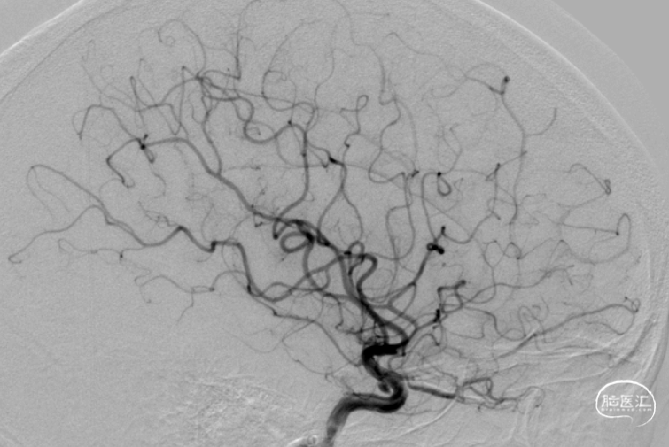

术前检查

DSA:双侧眼段动脉瘤